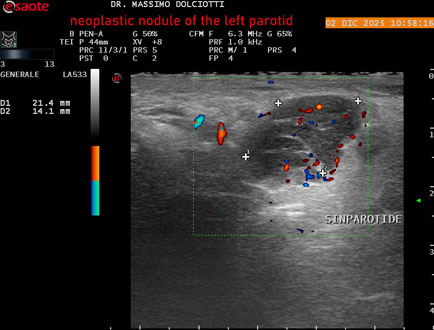

Data inserimento: 18/12/2025

Ecografia del: 02/12/2025

Strumento: Esaote MyLab Eight

Sonda: Lineare Multifrequenza 3-13 MHz

Età Paziente: F 70 anni

Motivazione dell'esame: tumefazione ed arrossamento in sede parotidea sinistra, nel 2003 k mammella sinistra operata e sottoposta a radio e chemioterapia.

Commento all'esame: le immagini ed il video documentano, alla parotide destra, nodulo ipoecogeno, a margini irregolari e frastagliati, con vascolarizzazione ad alto indice di resistenza, da ricondurre a nodulo neoplastico da tipizzare.

Conclusioni: nodulo neoplastico alla parotide sinistra (neoplastic nodule in the left parotid gland).